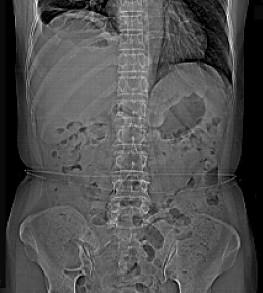

问题 女,59岁,发热、右上腹痛、右下肺呼吸音低,影像检查如图,最可能诊断是 ( )

选项 A、肝硬化腹水 B、大网膜膈下间位 C、膈下脓肿 D、肝包膜下出血 E、腹腔积液

答案 C